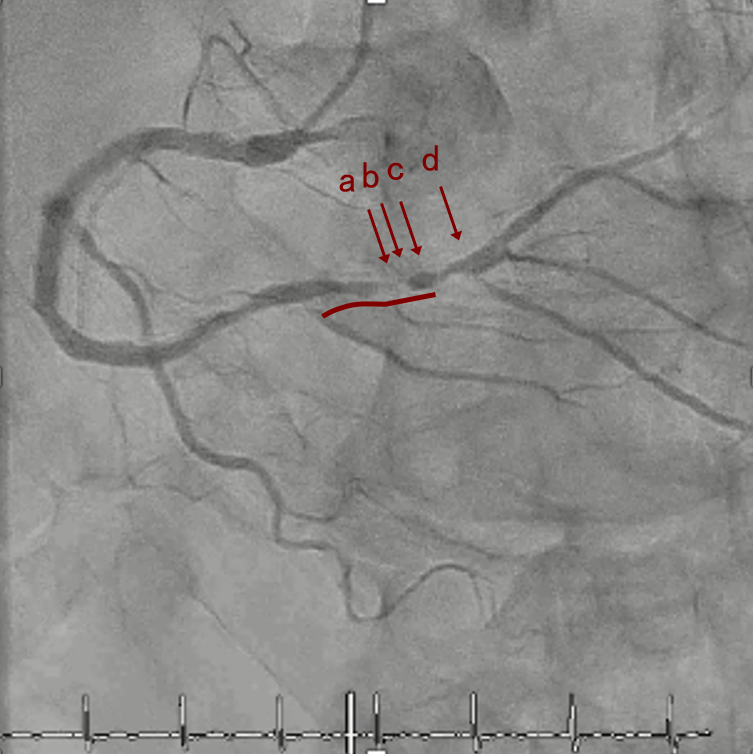

CAG

RCA distalの高度石灰化狭窄病変

IVUS imaging

IVUSでは8時方向からPD枝がはいいてくる。

PreのIVUSではaの部位のみlipid plaqueを認め削ることでdistal embolismのリスクがあり、そのほかは270度の偏心性石灰化であるがwire biasは良好。

OAS low speedによる引きを赤線の区間行う方針とした。